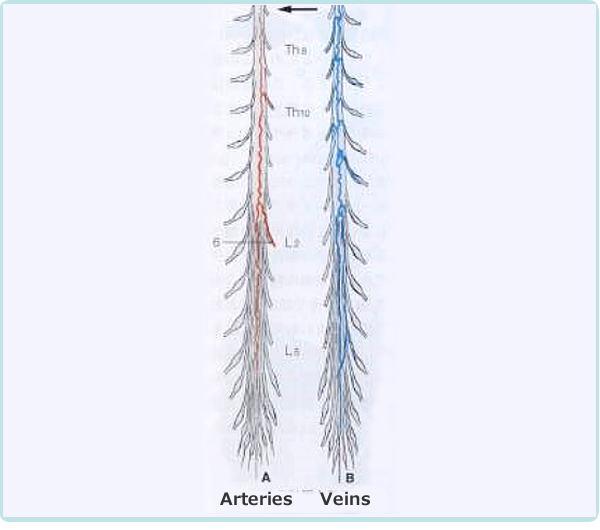

The mechanism of intermittent claudication is as follows. In scoliosis, the cauda equina nerve, which is located below the second lumbar vertebra. It resembles a horse's tail and is compressed by a deformed yellow ligament or vertebra causing pain and numbness in the lower extremities. The cauda equina nerve has longitudinally distributed blood vessels that supply oxygen and nutrients to the nerve root as shown in Figure 2-2.

As the lumen of the lumbar spinal canal narrows, the nutrient vessels of the caudal nerve are compressed and narrowed. When the lumbar spine kyphosis is strengthened by upper body loading (60% of body weight) during walking, the spinal canal is further narrowed and the pressure on the blood vessels becomes stronger. As a result, blood flow to the cauda equina nerve deteriorates, causing pain and numbness in the lower limbs, making walking difficult (intermittent claudication).

Thus, the mechanism of the pain, numbness, and burning sensation in the hip and lower limbs during walking is due to the blood flow disturbance caused by the compression of the blood vessels that nourish the spinal cord. New meridian therapy effectively improves numbness and pain during walking without the need for surgery. The mechanism of this effect is thought to be that it improves blood flow around the spinal canal and spinal blood vessels, reduction of edema due to inflammation of the tissues around the spinal canal, thereby improving the narrowing of the spinal canal. At the same time it repairs and expands the spinal blood vessels, thereby improving blood flow.